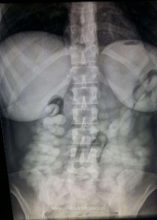

Potrivit Poliţiei de Frontieră, în data de 10.11.2017, ora 15.10, la P.P.F. – Aeroport Henri Coandă, s-au prezentat pentru a intra în ţară, călătorind din Brazilia, via Zurich, trei cetăţeni brazilieni, două femei Patricia C. şi Verice R., în vârstă de 40, respectiv 41 de ani, precum şi un tânăr, Weslley L. în vârstă de 19 ani. Cu ocazia efectuarii formalităţilor de frontieră, în urma unei analize de risc, poliţiştii de frontieră din cadrul P.P.F. Henri Coandă, împreună cu lucrătorii vamali, au procedat la efectuarea unui control amănunţit asupra celor trei persoane şi bagajelor acestora. Existând suspiciuni că transportă substanţe interzise, persoanele în cauză au fost supuse unui control cu raze X, cu aparatul aflat în dotarea Poliţiei de Frontieră din cadrul Aeroportul Internaţional Henry Coandă. Cu această ocazie s-a constatat că două dintre persoane, Verice R. şi Weslley L. aveau zeci de capsule ingerate în stomac. Cetăţenii brazilieni au fost preluaţi de către poliţiştii din cadrul B.C.C.O. Ilfov, în vederea continuării cercetărilor, fiind conduşi la Spitalul de Urgenţă Floreasca pentru expertiza de specialitate a capsulelor, care conţineau o substanţa de culoare albă. În urma analizei de laborator, substanţa, în greutate aproximativa de 2.000 de grame, a reacţionat pozitiv ca fiind cocaină. În cauză, pe numele celor doi cetăţeni brazilieni se efectuează cercetări pentru săvârşirea infracţiunii de trafic de droguri de mare risc şi trafic internaţional de droguri de mare risc. În baza probatoriului administrat, procurorii D.I.I.C.O.T. au dispus reţinerea pentru 24 de ore a lui Weslley L. şi Verice R., acestia fiind prezentaţi Tribunalului Bucureşti cu propunerea de arestare preventivă pentru o perioadă de 30 zile.